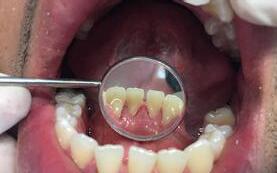

Caso 1

Se presenta un paciente de 29 años de edad. Al interrogatorio clínico refiere no tener alteraciones sistémicas y que actualmente no está tomando ningun medicamento, acude a la consulta odontológica para que le realisen una limpieza. En la revision clínica se observa la presencia de bioplaca y con sarro en los organos dentarios (OD) del 32 y 42 por la superficie vestibular. Por lo que se indica una profilaxis, se procedió de la siguiente manera, tinción de la bioplaca (Figura 1), realizándose el levenatmiento del índice epidemiológico IHOS. Se obtuvo el promedio de

Dentista y Paciente 46 Caso clínico

Figura 1. Frente de inicio.

A B

Figura 2. Vista lingual inferior dientes con sarro.

la bioplaca, el cual fue bajo según el IHOS 0.6 y el sarro se localizó en los OD Inferiores 32 y 42 por las superficies vestibular y lingual.

En la Figura 2 se ven los organos dentarios del 32 al 42 con sarro en la superficie lingual abarcando menos del tercio medio.

Se llevó a cabo la profilaxis para retirar el sarro (Figura 3), una vez eliminado se procedió al cepillado de todas las superficies dentarias.

Una vez terminada la limpieza dental se revisó la técnica de cepillado que llevaba a cabo el paciente, la cual era adecuada. Se le indicó que para evitar la acumulación del sarro la utilización de auxiliares de limpieza como parte de las acciones de promoción de salud (Figura 4). Y el alumno de primer año le enseño el manejo del hilo dental como complemento para el control de bioplaca. Citando nuevamente al paciente al mes del tratmiento.